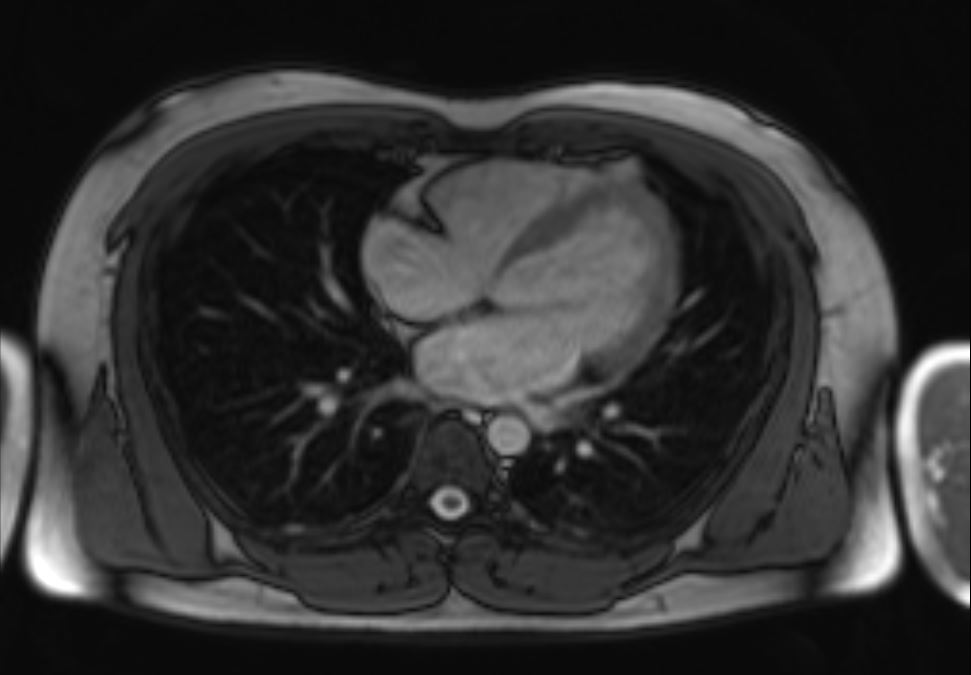

Further history revealed that he had brief flulike symptoms prior to onset of chest pain. He added he also recently consumed ¡®Honey¡¯ that he purchased from social media- Tik Tok. Further investigation revealed that there the purchased botanical honey contained kratom in its ingredient. Blood investigation showed rise of creatinine kinase from 562 U/l to 583 U/l as well as troponin T from 762 pg/ml to 875 pg/ml. Due to the nature of his diagnosis of MINOCA, a cardiac MRI was done, however showed absence of myocardial inflammation, edema, fibrosis or infiltration.